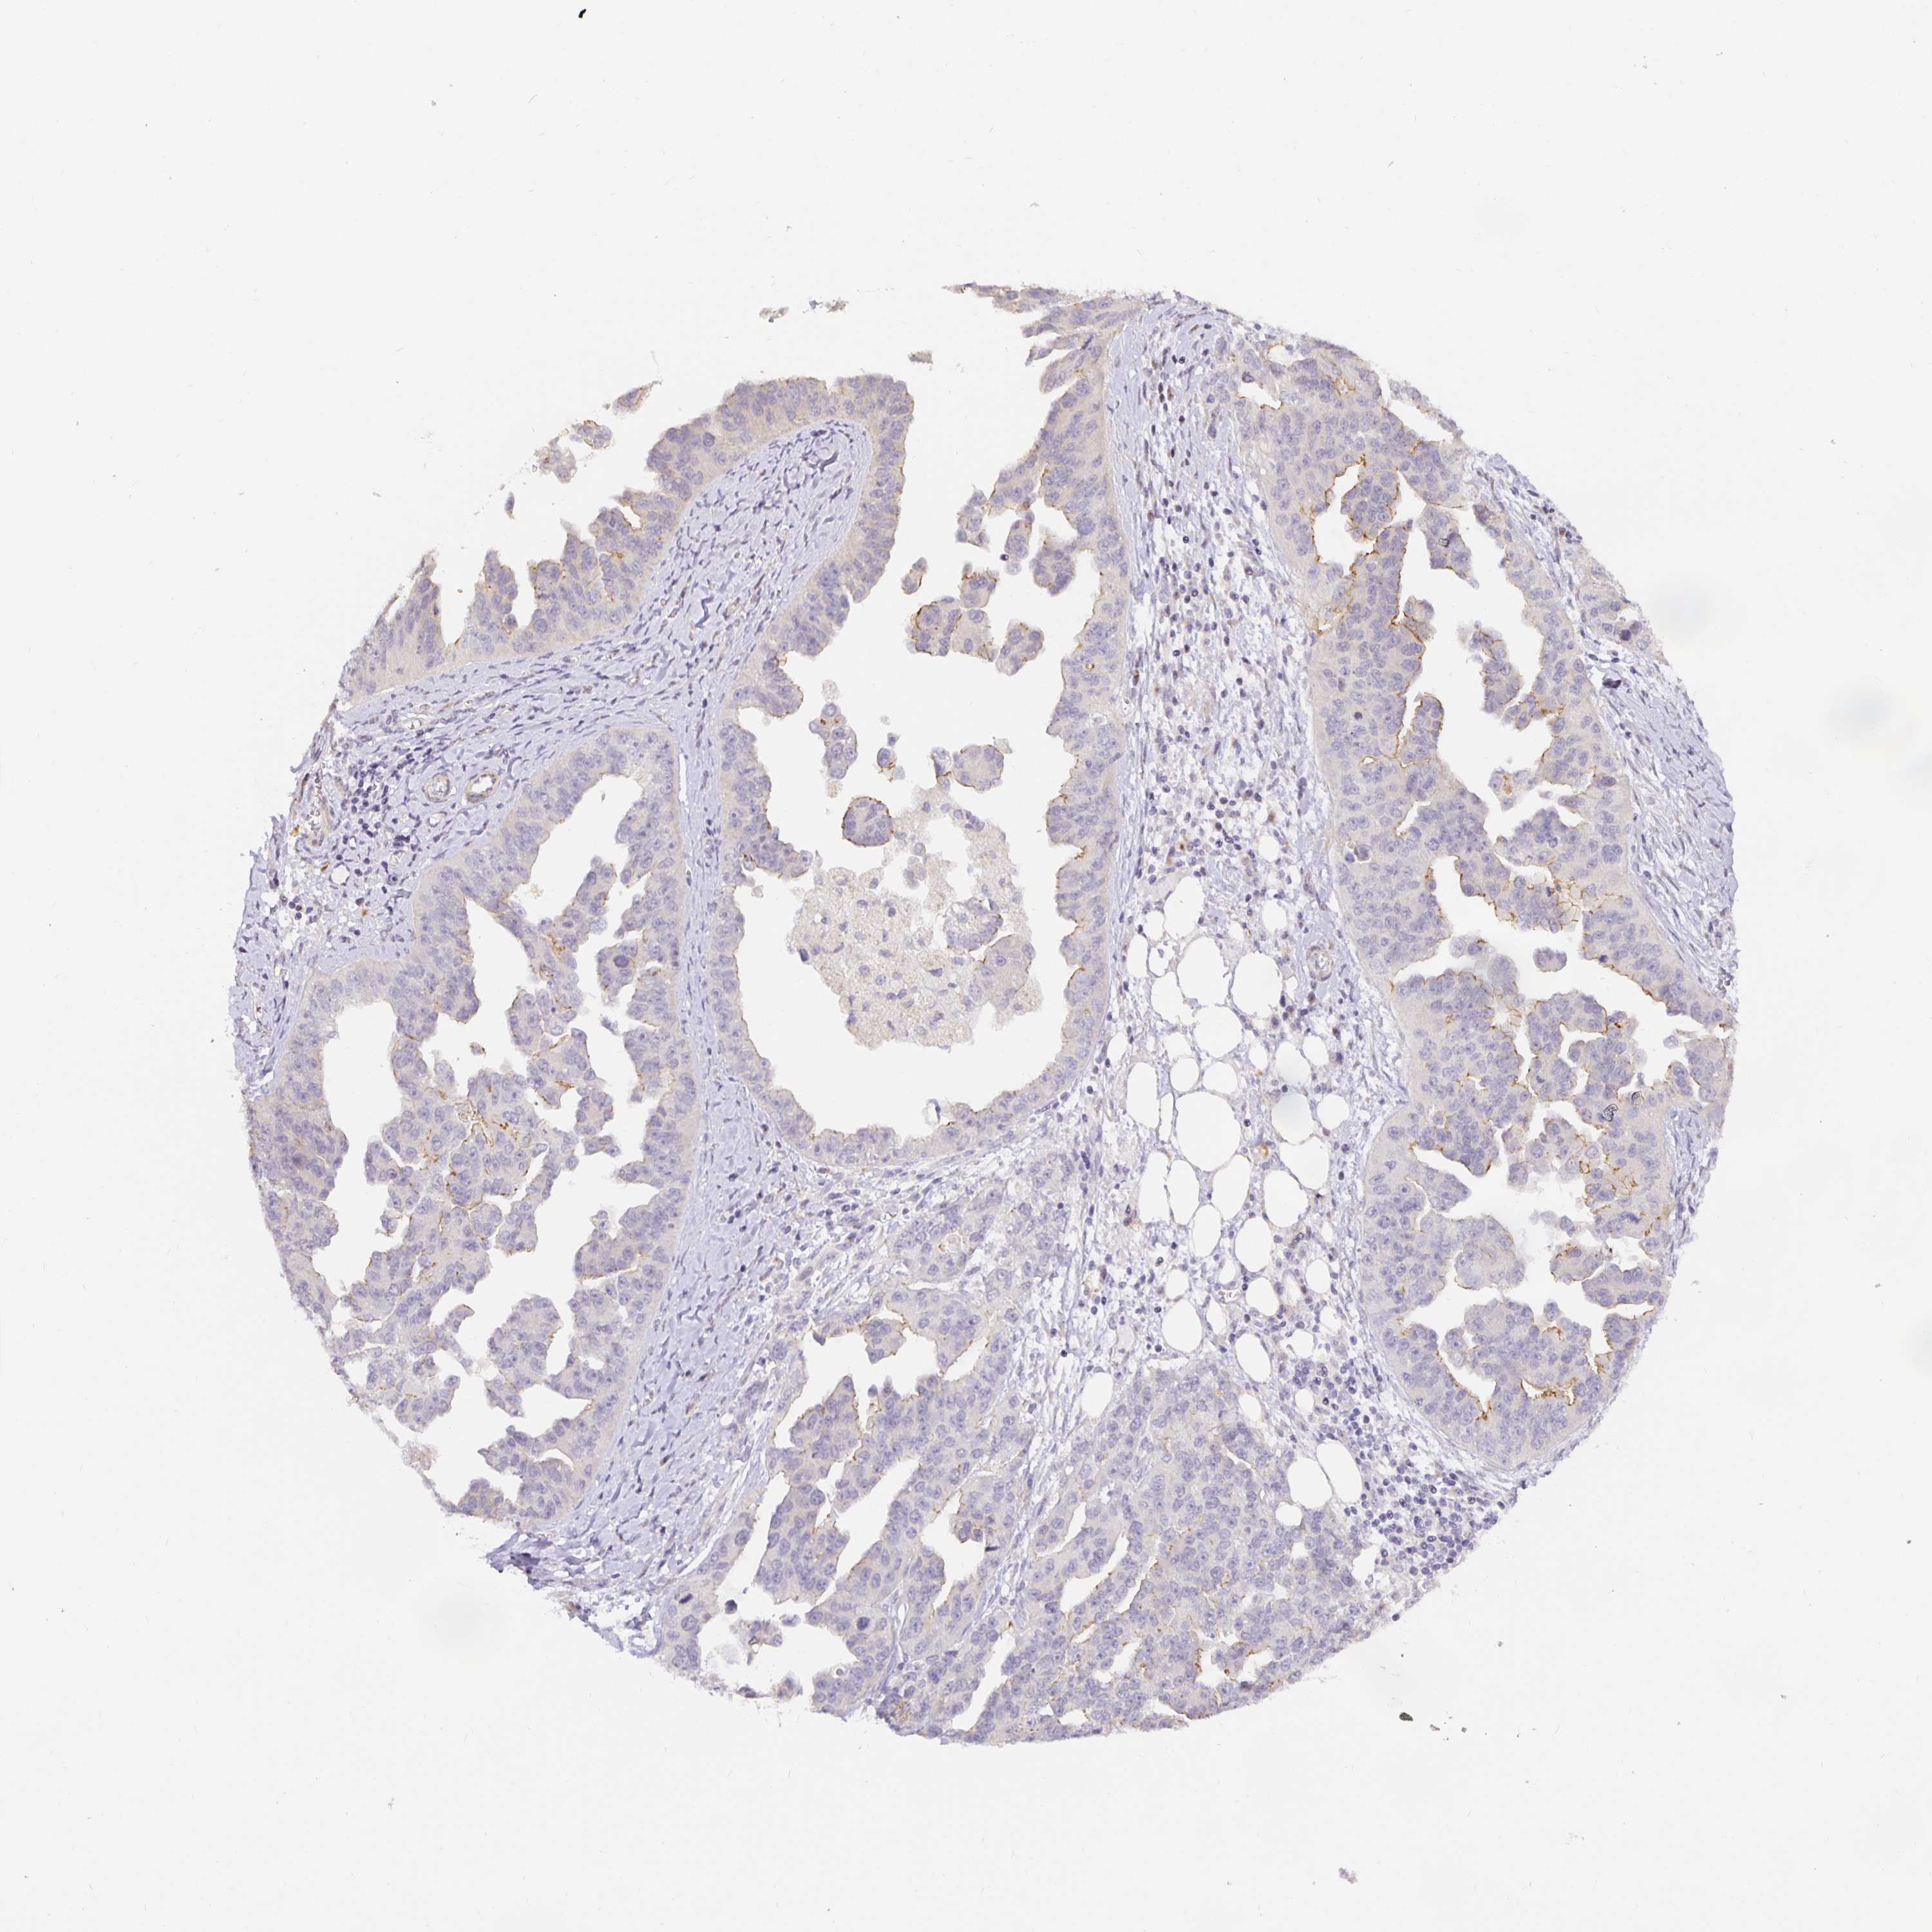

OVARIAN CANCER - Protein expressioni

A mouse-over function shows sample information and annotation data. Click on an image to view it in a full screen mode. Samples can be filtered based on level of antibody staining by selecting one or several of the following categories: high, medium, low and not detected. The assay and annotation is described here.

Note that samples used for immunohistochemistry by the Human Protein Atlas do not correspond to samples in the TCGA dataset.

Antibody stainingi

Antibody staining in the annotated cell types in the current human tissue is reported as not detected, low, medium, or high, based on conventional immunohistochemistry profiling in selected tissues. This score is based on the combination of the staining intensity and fraction of stained cells.

Each image is clickable and will lead to virtual microscopy that enables deeper exploration of all samples and also displays staining intensity scores, fraction scores and subcellular localization as well as patient and tissue information for each sample.

Antibody HPA053337

Antibody CAB013244

Staining

High

Medium

Low

Not detected

Intensity

Strong

Moderate

Weak

Negative

Quantity

>75%

75%-25%

<25%

None

Location

Nuclear

Cytoplasmic/membranous

Cytoplasmic/membranous,nuclear

Cystadenocarcinoma, serous, NOS

Cystadenocarcinoma, mucinous, NOS

Carcinoma, endometroid

Carcinoma, NOS